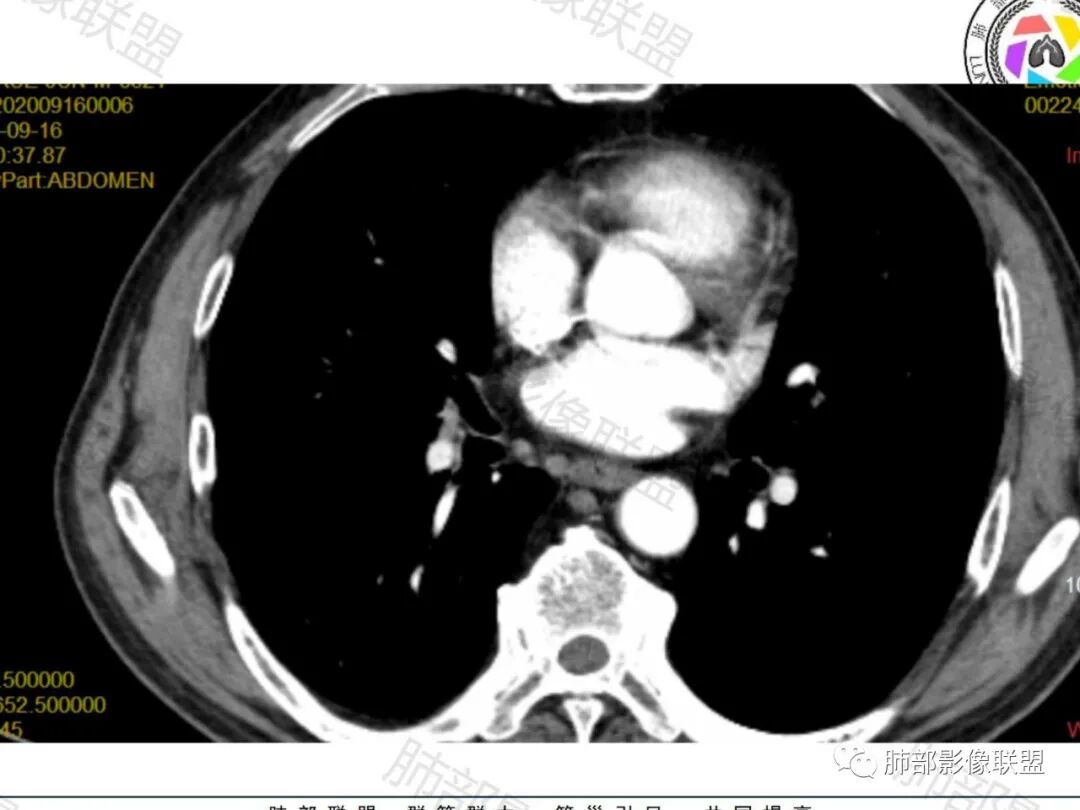

右肺下叶一类圆形肿块影,内缘边缘光滑,外缘边界模糊,可见磨玻璃影,整体以彭隆为主,部分边缘包绕支气管,平扫密度尚均匀,增强后不均匀强化,部分与膈肌黏连,临床,62岁男性,无症状,考虑恶性:腺癌,鳞癌,神经内分泌癌,肉瘤

老年人,偶然发现,右肺下叶类圆形软组织占位,密度较均匀,病灶边缘光滑,无毛刺分叶,支气管血管受挤压向外移位,增强病灶强化较均匀。考虑恶性肿瘤,外向内生长,肉瘤,肉瘤样癌,癌肉瘤,其次神经内分泌癌。

老年男性,右肺下叶软组织肿物,整体外形光整,周围组织推挤,可见血管贴边,貌似又有血管进入,整体强化均匀,考虑良性可能大,硬化性肺细胞瘤?鉴别sft

老年男性,偶然发现,说明平时没有症状,边缘光整,血管贴边,整体强化均匀,倾向于良性或者低度恶性(PSP?类癌?)

老年男性,肿瘤标志物高,右肺占位,边界清楚,内部密度均匀,坏死不明显,无明显分叶,血管贴边,考虑PSP,老年男性,肿块大,需鉴别恶性,肉瘤样癌?高分化鳞癌?

男性,62,胆结石入院胸部CT偶然发现占位。肿标稍增高,右肺下叶胸膜下肿块,边缘尚清,密度较均匀,增强明显强化,血管贴边,空气新月征?静脉期可见低强化区,首先考虑PSP,鉴别肉瘤样癌及神经内分泌肿瘤

老年男性,右肺下叶肿块,边缘光整,血管贴边,部分血管进入,整体强化尚均匀,考虑大细胞癌,鉴别PSP、SFT

右肺下叶类圆形软组织肿块,病灶边缘光滑,无明显毛刺分叶,支气管受压推移,血管贴边,部分血管进入病灶,增强病灶强化不均匀,内可见低密度,病灶与右侧膈肌分界不清,考虑神经内分泌肿瘤,大细胞癌。鉴别PSP

老年男性,肿瘤标志物高,右肺下叶类圆形肿块,宽基底与胸膜相连,边缘光整,密度均匀,周围气管及血管受压推移,延迟强化,其内见纤细血管,似有小低密度灶,首先考虑间叶组织恶性肿瘤,良性平滑肌瘤、纤维瘤不除外

患者中老年男性,检查发现右下肺占位。查肺癌标记物稍有升高。血常规白细胞计数稍降低。胸部CT:右肺下叶后基底段类圆形肿块,边缘光滑,边界清楚,周边见气管受压扩张,增强轻度强化,内见点状低密度影,见血管贴边。综合考虑良性过低度恶性病变,PSP可能,其它恶性肿瘤待排。

支气管,血管均受压推移,类圆形占位,无分叶,无毛刺,光滑表面,明显均匀强化,倾向于psp,鉴别错构瘤,肉瘤,肉瘤样癌,类癌等神经内分泌肿瘤,转移,imt。